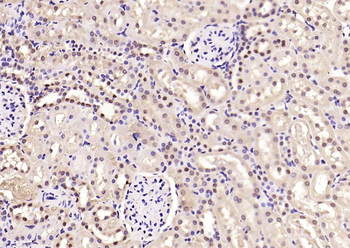

100 μl, 200 μl, 50 μlPhospho-SMAD5 (Ser463 + Ser465) Recombinant Rabbit Monoclonal Antibody [orb559123]

ICC, IF, IHC-Fr, IHC-P, WB

Mouse, Rat

Human, Mouse, Rat

Rabbit

Recombinant

Unconjugated

50 μl, 100 μlPhospho-Smad3 (Thr179) Rabbit Polyclonal Antibody [orb313112]